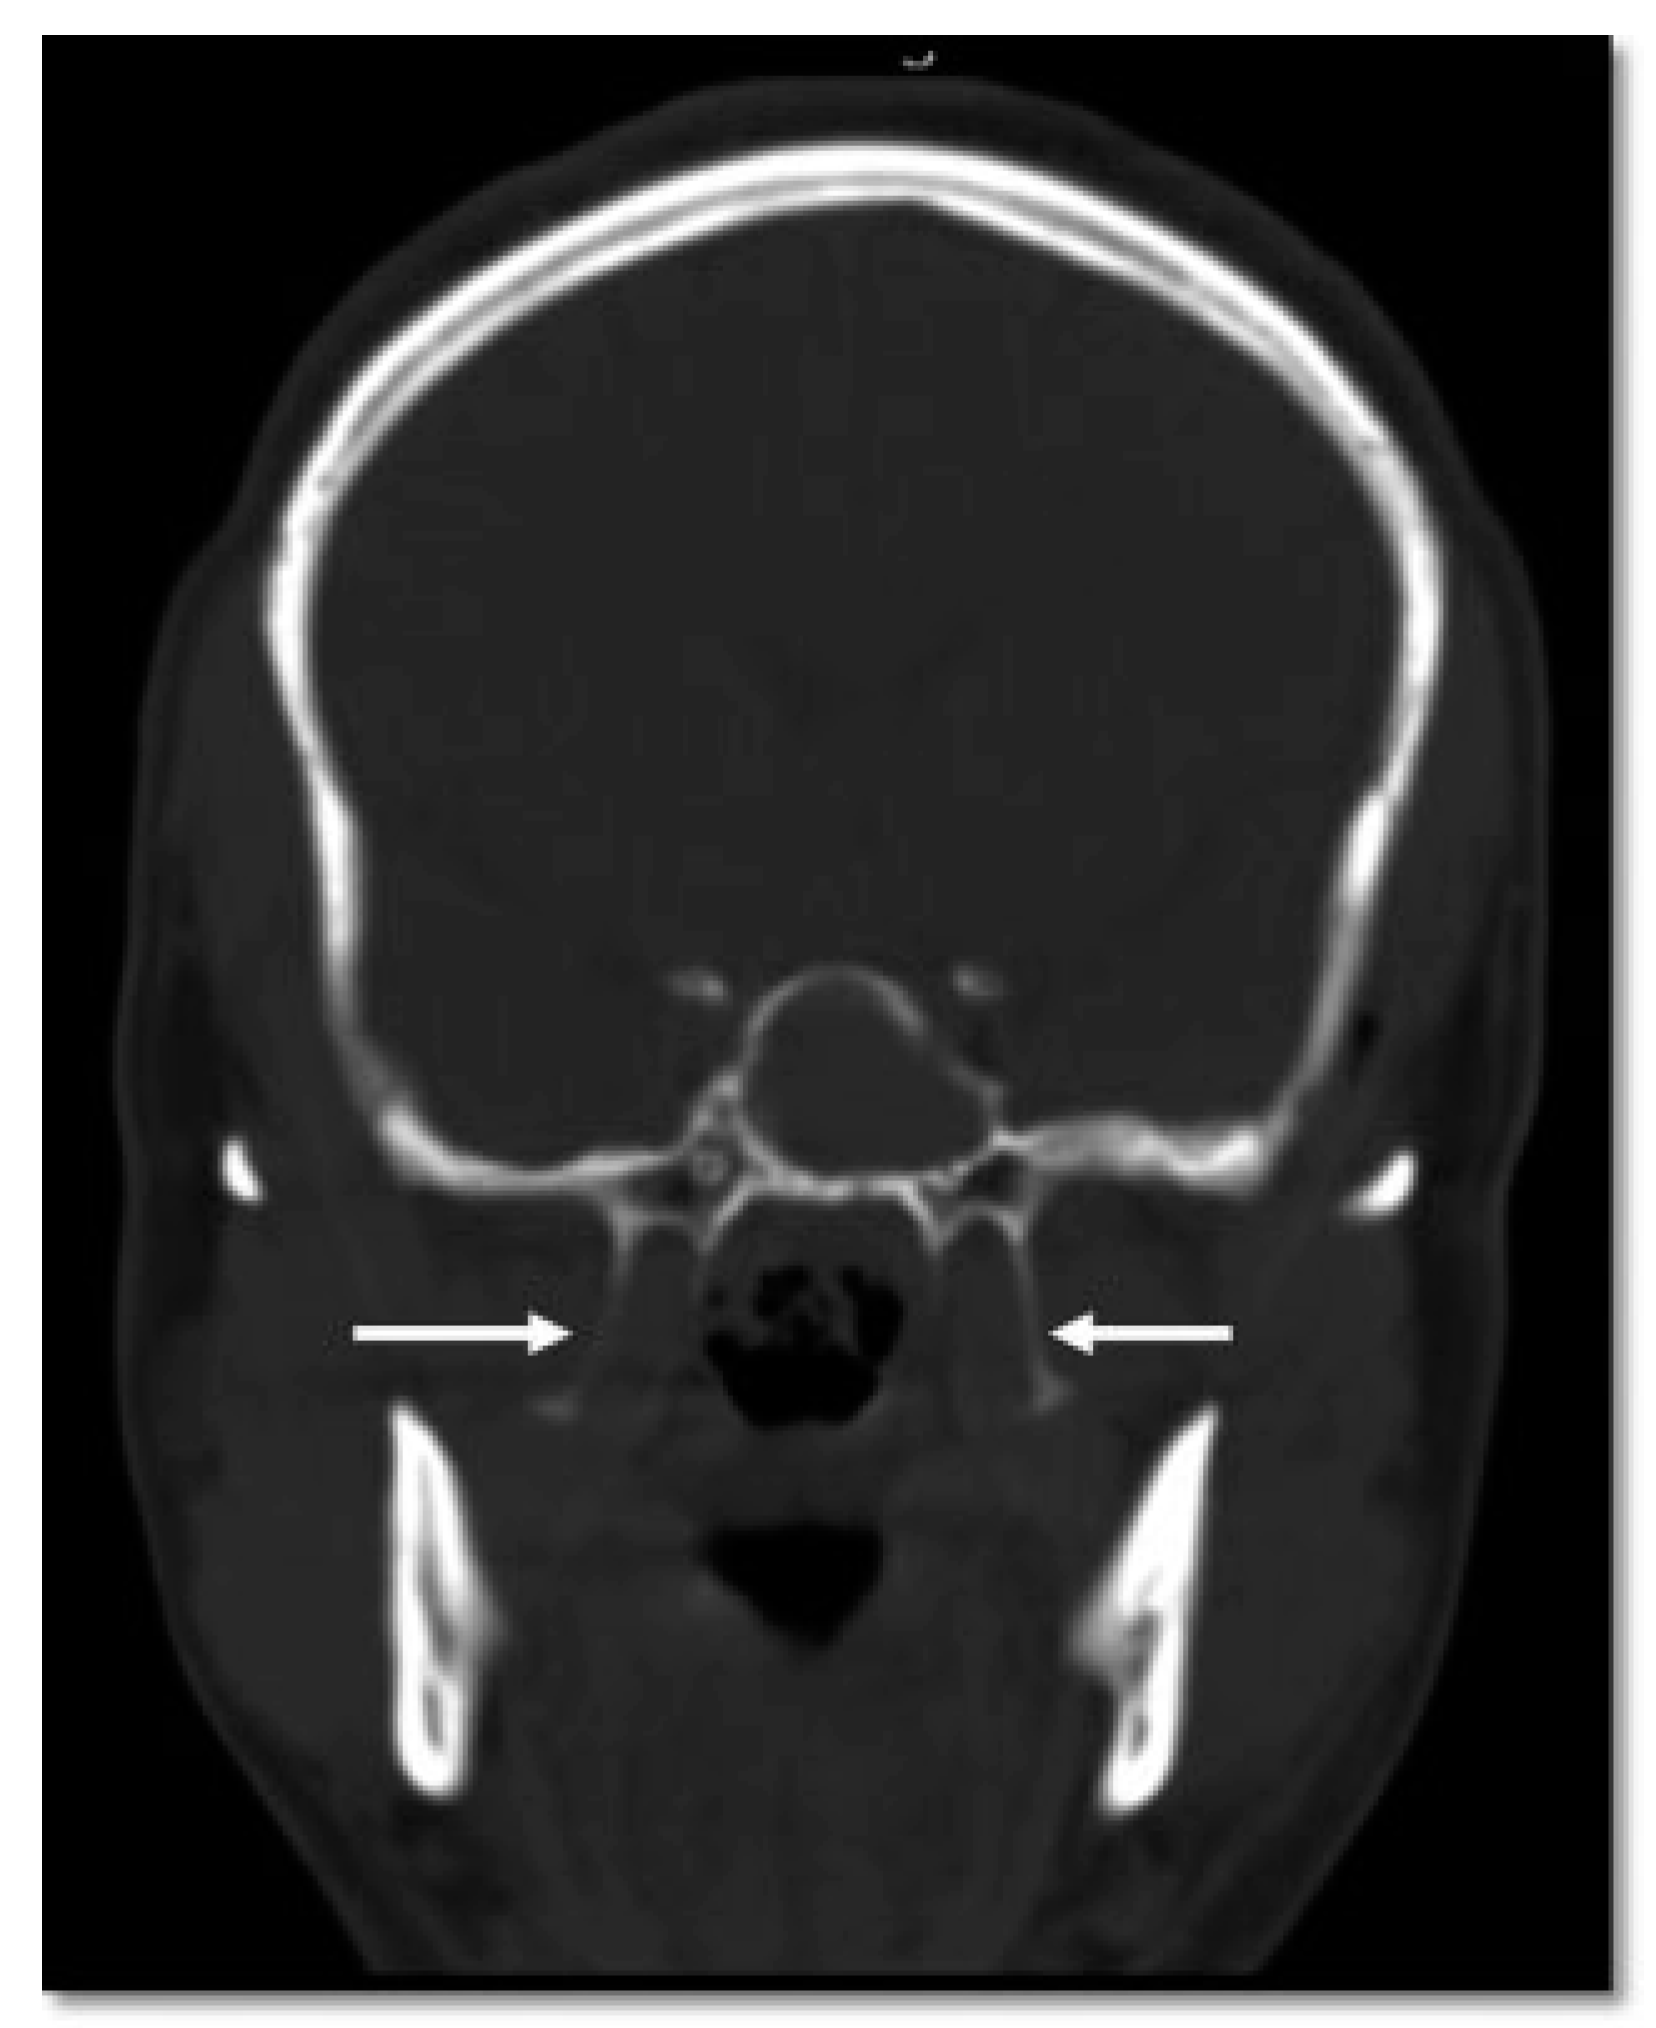

- Additional line extending from the pyriform aperture to the infraorbital rim of the same side (60%).

- Additional line extending from the infraorbital rim to the Le Fort fracture line.

- Additional line extending from the pyriform aperture to the lateral wall of orbit, without breaking the infraorbital rim of the same side (5.4%).

- Additional line extending from the infraorbital rim through the canine fossa to terminate as a fractured dentoalveolar segment of the same side, involving the fractured segment (10.9%).

- Pterygoid plates are not fractured (23.6%).

- D1: Additional Line Extending from the Pyriform Aperture to the Infraorbital Rim of the Same Side (34.5%)

- D2: Additional Line Extending from Infraorbital Rim to the Le Fort Fracture Line (25.4%)

- D3: Additional Line Extending from Pyriform Fossa to Lateral Wall of Orbit, without the Fracture of the Infraorbital Rim of the Same Side (5.4%)

- D4: Additional Line Running from the Infraorbital Rim through the Canine Fossa to Terminate as a Fractured Dentoalveolar Segment of the Same Side (10.9%)

- D5: Pterygoid Plates Are Not Fractured (23.6%)